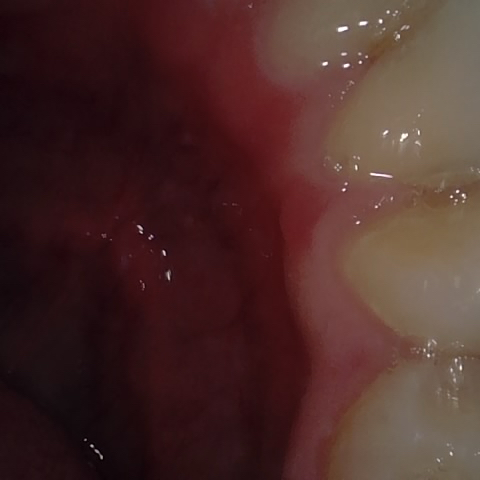

Annotated as "Bad"